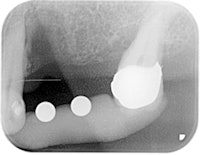

Figure 2: Radiograph with measuring balls.

Because of a severe endodontic/periodontal lesion, tooth 24 of a 59-year-old woman was beyond saving. A radiograph with measuring balls was taken three months after extraction, illustrating the extent of the preceding osteolytic process (figure 2).